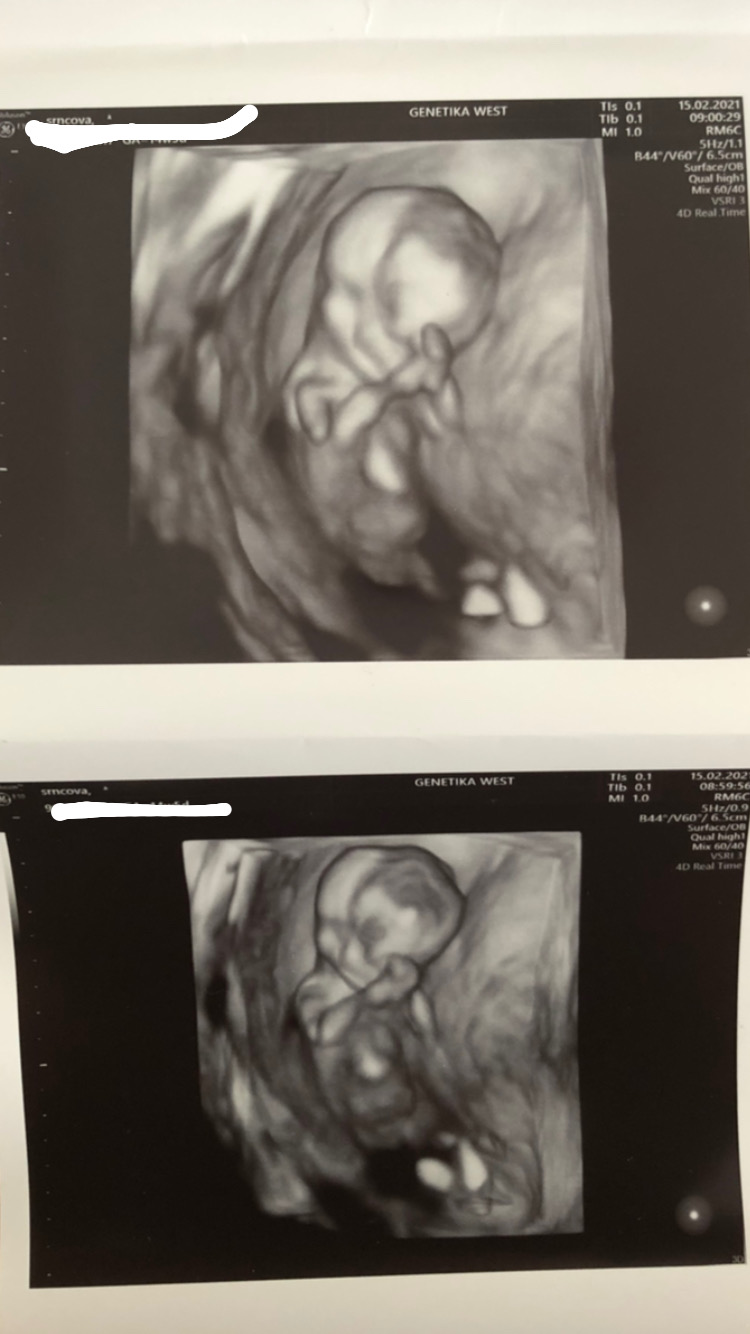

@adelaa1234 krásné fotecky 😍. Jsem ráda, že máš všechno v pořádku. A tobě už je líp?

@adelaa1234 no to je tak krásný🙂 taková malá princezna🙂

@jade85 ano tipla🥰 říkala , ze se málokdy zmýlí 😂😊 tak uvidíme na druhem scrweningu, jestli mi tu holčičku potvrdí znovu 😊

@adelaa1234 nám to řekl jako první věc na screeningu. Bylo to krásně vidět. Říkal, že to pozná podle toho pohlavního vycnelku, že u holčiček je víc k tělu a u kluků víc vzpřímeny. Ale samozřejmě to může být ještě jinak.

@adelaa1234 Ty jo to je krásný 😊 já jsem zvědavá jestli u mě bude vidět už pohlaví až půjdu na ten screening 😁 to budu 12+4. Kolikátý jsi týden?

@siima12 určitě jo😊😊 dneska 12+5 🥰